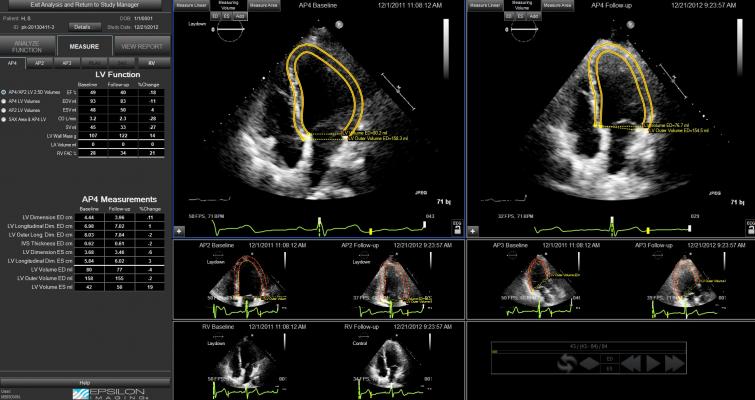

June 17, 2016 — Epsilon Imaging Inc. announced a research study was presented at the American Society of Echocardiography (ASE) 2016 conference from a team at the University of Chicago. The study demonstrated that the semi- automated volumes and ejection fraction (EF) generated with Epsilon’s EchoInsight strain imaging are accurate, efficient and may improve standardization among readers when interpreting the left ventricle (LV) with echocardiography.

The study, “Semi-Automated Assessment of Left Ventricular Volumes and Global Longitudinal Strain,” was presented by Roberto Lang, M.D., and Diego Medvedofsky, M.D., et al. Transthoracic images from 30 patients with a wide range of LV volumes and EF were analyzed by an expert using conventional methodology to trace LV endocardial borders and obtain volumes, EF and global longitudinal strain (GLS). With the same parameters, the patient studies were then analyzed with EchoInsight, and with its semi- automated techniques for volumes and EF based on manual enrollment of region of interest with speckle tracking strain imaging. Minimal editing was performed as necessary. In addition, three less experienced readers (first-year cardiology fellows) performed the same analyses and their measurements were compared to the experienced reader’s.

Time required for the automated analysis with editing was approximately 1 minute per patient, compared to 2 minutes for conventional manual analysis. Parameters obtained with the semi-automated approach and analysis of expert versus less experienced readers were in excellent agreement.

“Although LV volumes and GLS are clinically important and recommended by the current echocardiographic chamber quantification guidelines, these measurements, especially strain, are not routinely performed. Our study found that the semi-automated technique with EchoInsight is feasible, fast and provides quantitative parameters of LV volumes, EF and GLS, which are comparable to conventional measurements, even when performed by less experienced readers,” said Lang, director of noninvasive cardiac imaging laboratories at University of Chicago Medicine. “EchoInsight and its automated approach to cardiac function measurements with strain imaging has the potential to facilitate the workflow in a busy echo labor and allow routine use of LV volumes and GLS in the every-day practice.”